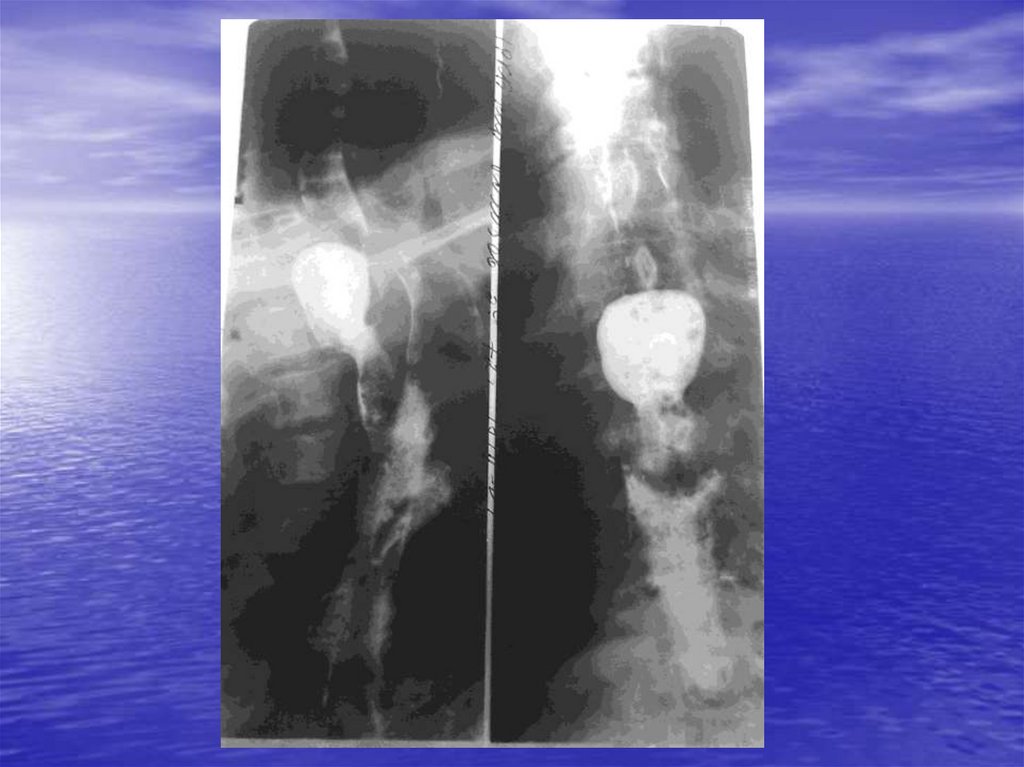

А) Ахалазия кардии

Б) Недостаточность кардии